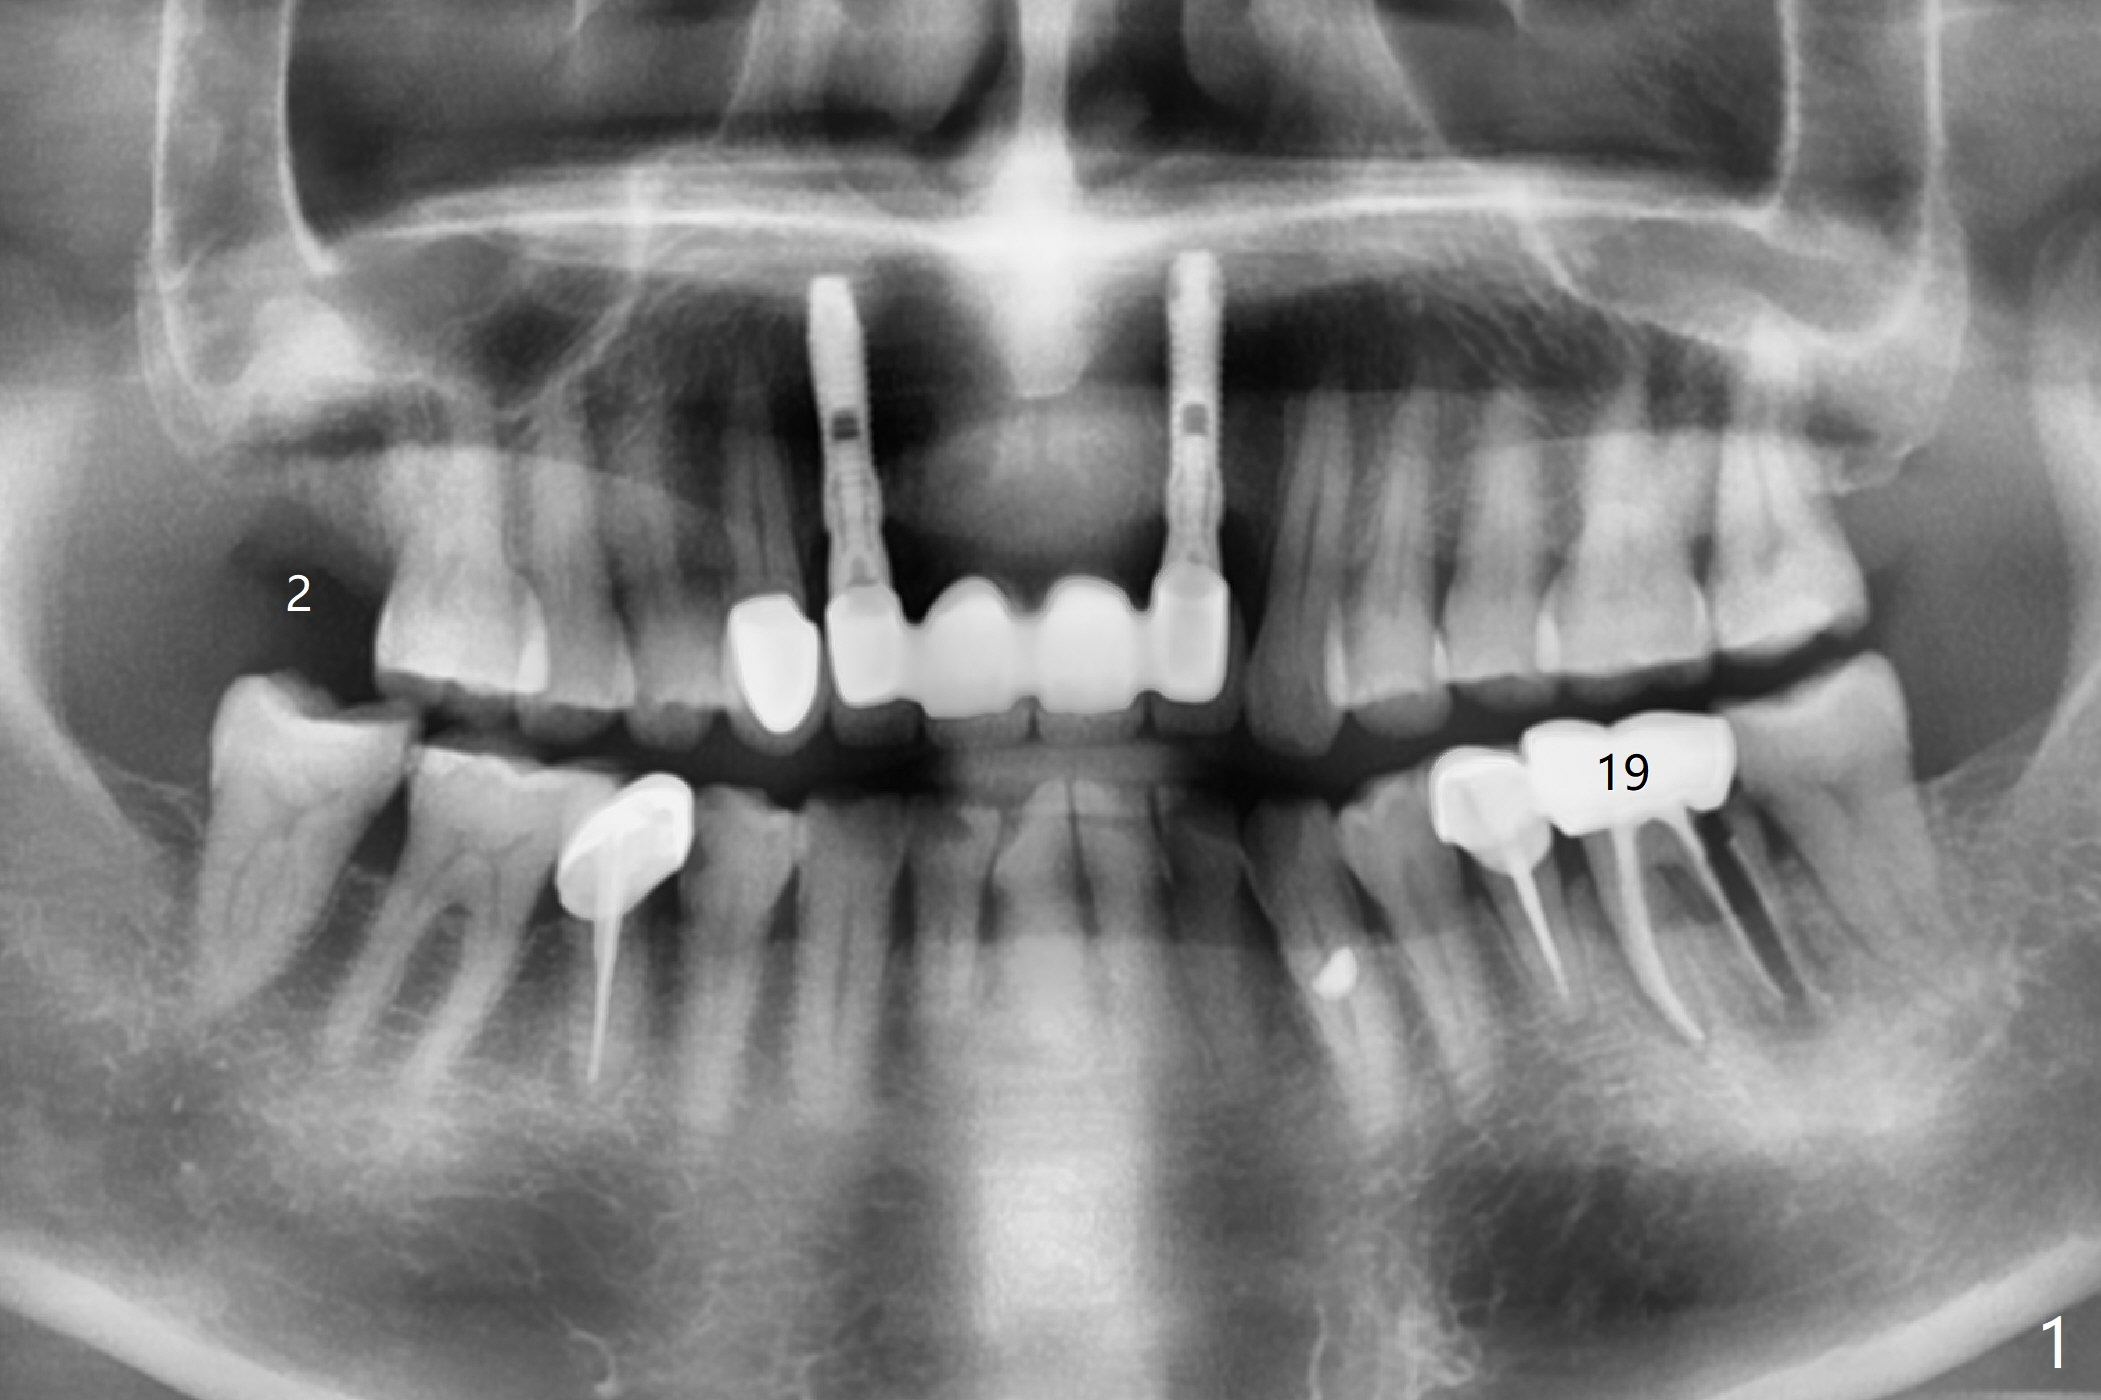

A 55-year-old man with chronic sinusitis, gagging and bruxism returns for #2 implant redo nearly 4 months post implant removal and bone graft (Fig.1). It appears that the site heals with ~ 860 HU (Fig.2). Considering history of chronic sinusitis, a 5x10 mm implant seems too long (Fig.3). For active gag reflex, a 5x11.5 mm implant may be also too long at #19 (Fig.4).